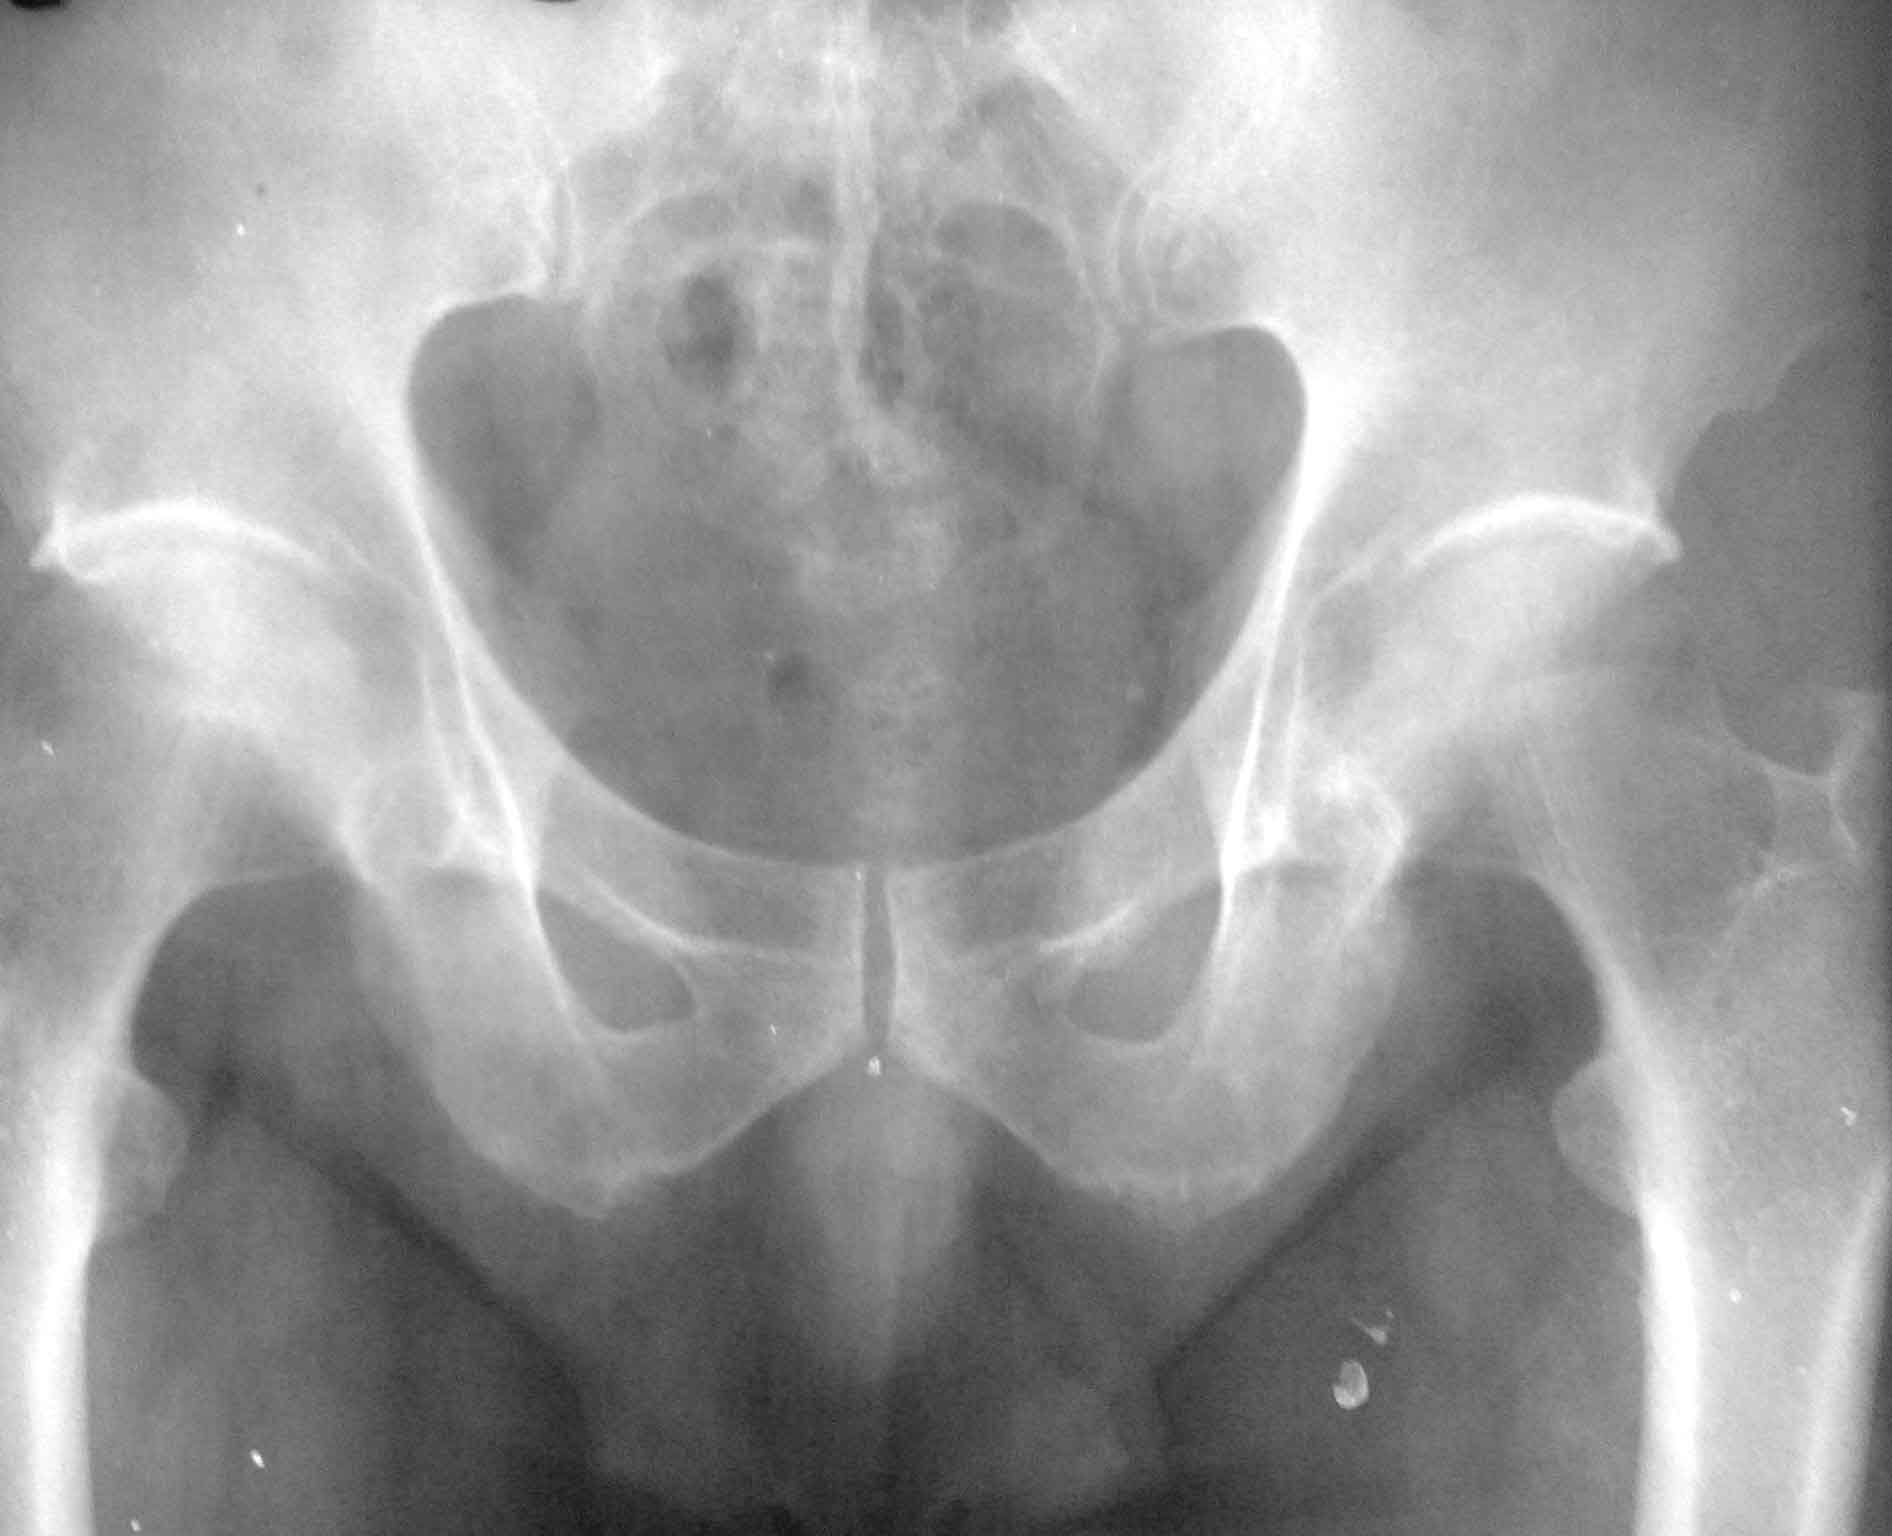

男62岁,右下肢不适,说不出的难受3年,夜间严重,难以入睡,须下地活动或用力捶击下肢才有所缓解,白天无明显疼痛。右坐骨结节有压痛不串射,下肢抬高试验(-)。腰椎ct无异常,骨盆片右坐骨结节与对侧对比似有缺损,是否病变?